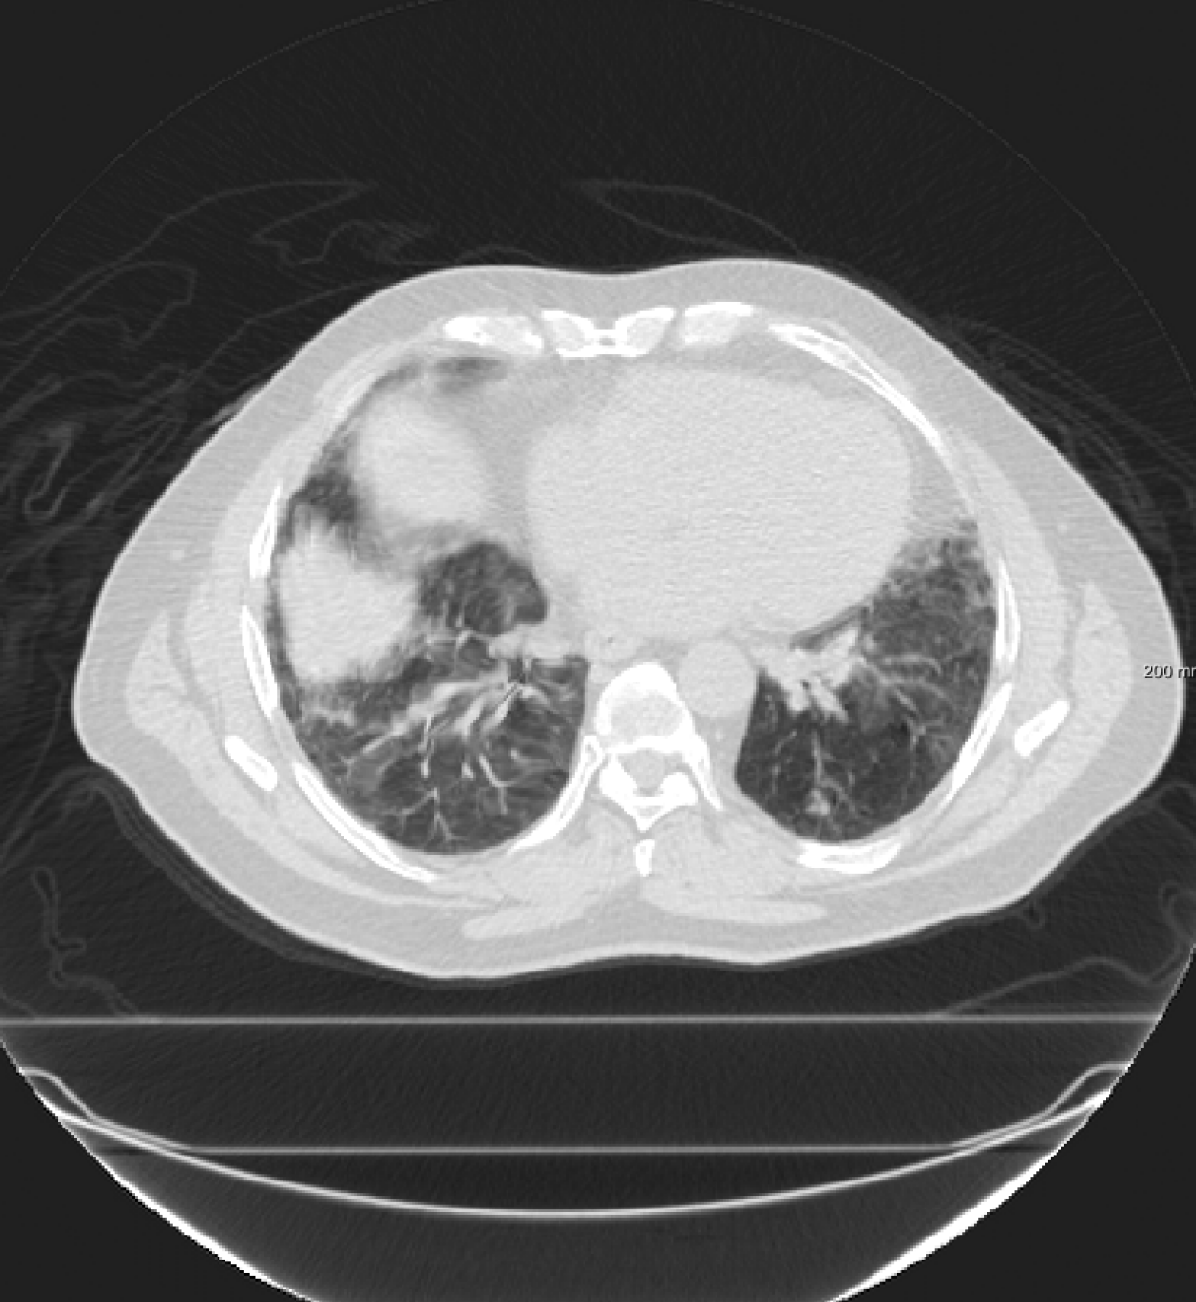

For the DIR-Lab-4DCT database, a comparison between RegNet and affine, B-spline (three resolutions), an advanced conventional registration method using sliding motion (Berendsen et al., 2014) and three other CNN-based methods (Eppenhof and Pluim, 2018; de Vos et al., 2019; Sentker et al., 2018) is available in Table IV. It can be seen that training with “S+M” improved performance slightly with respect to just “S”. Adding the respiratory motion category improved performance substantially, as these are inhale-exhale pairs; this is predominantly caused by the patients where the TRE after affine registration was still quite large. An example visualization is also available in Fig. 5(f), showing that adding the respiratory motion category can align images better in the diaphragm region. The advanced conventional registration method that leverages sliding motion (Berendsen et al., 2014) is still better than RegNet. Note that RegNet was not trained on the DIR-Lab-4DCT data, similar to Eppenhof and Pluim (2018); Sentker et al. (2018). However, de Vos et al. (2019) and Eppenhof and Pluim (2018)-DIR methods were trained on the same database but using cross-validation to report the results. Also note that the results reported in Sentker et al. (2018) are averaged over all phases of DIR-Lab-4DCT (T00 to T10), while the results of other CNN methods (including RegNet) are reported between the maximum inhale and maximum exhale phase (T00 and T50). These reported results are therefore likely somewhat better than the results for T00 and T50 only.